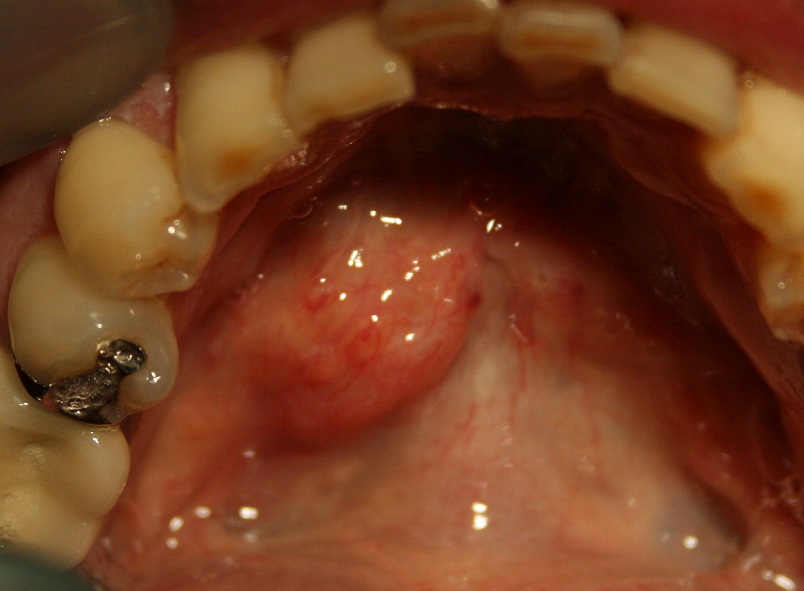

唾石症の治療法として、手術で詰まっている石を取り除く方法があります。. 口腔内のどの位置にあるかを特定したら、局所麻酔を用いて粘膜を切開し、石を取り除きます。. 石が大きい場合や感染を繰り返している場合、もしくは唾液腺の機能が消失して.. 唾石症とは、唾液腺(唾液を作っているところ)や唾液が通る管内に石ができてしまう病気です。食事時に耳の下、顎の下(唾液腺)が繰り返し腫れたり、痛くなったりします。根本的治療は手術により唾石を摘出することです。